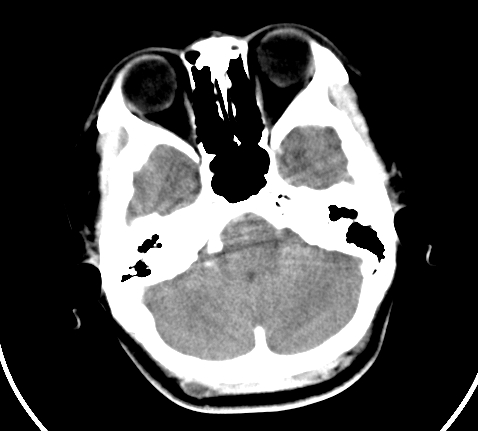

胸部

神经纤维瘤病

支持神经纤维瘤。